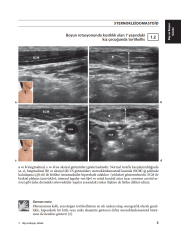

Kas-iskelet ultrasonu kullanıcıya bağlıdır, bu nedenle bir akıl hocalığı ve 'bakım' eğitimiyle güçlü bir şekilde eğitime ihtiyaç duymaktadır. Buna göre, bu kitabın asıl amacı, en sık taranan kas-iskelet patolojileri ile ilgili birçok örnek sunmak ve böylece uzun süreli denetlenen eğitimin boşluğunu doldurmaktır. Kitabın bölümleri, anatomi atlaslarındaki gibi, baş ve boyundan başlayıp ayaklarına kadar olan bölgeler şeklinde düzenlenmiştir. Her bölümde, alt bölümler de anatomik yapılara göre düzenlenmiştir. 500 görüntü bulunmaktadır. Metin esas olarak klinik / fizik muayene bulguları içeren uzun şekil içeriklerine dayanmaktadır. Önemli bir nokta da, kitabı okurken birçok sayfanın altındaki "Uzman Notu" olarak adlandırılan parçaları göreceksiniz. Bu yorumlar elbette kitabın en seçkin tarafıdır.